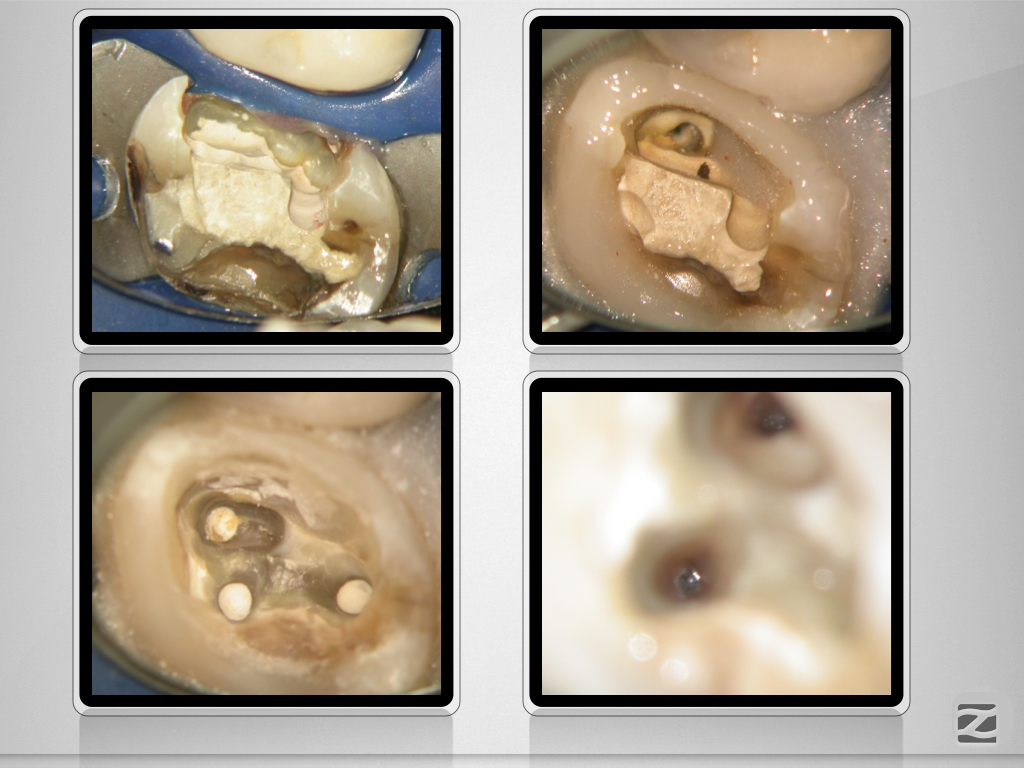

27D.005

Praxistauglicher Kompromiss